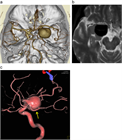

1. 未破裂脳動脈瘤の診断は、カテーテル法によるDSA:digital subtraction angiographyおよびその3次元血管撮影像がゴールドスタンダードである。3D-CTA:3次元ヘリカルコンピュータートモグラフィー、MRA: magnetic resonance angiographyなどは低侵襲な代替え診断法として未破裂脳動脈瘤の診断および治療に用いることが妥当である(推奨度1、J)